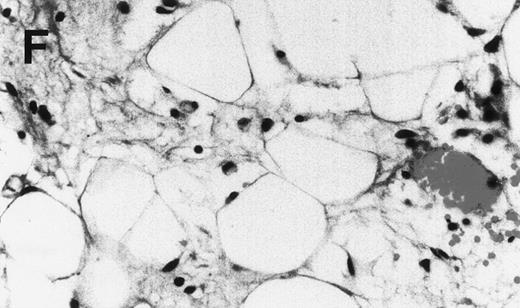

In the experiments in which cells recovered from the hosts were transferred to secondary (2 experiments) and tertiary hosts (1 experiment), all hosts developed myeloma with the typical manifestations. Within the experimental conditions and with the limitation of the small sample size, development of myeloma and the time to initial detection of hIg did not appear to correlate with the number of plasma cells inoculated. In contrast to hosts injected with purified myeloma plasma cells, hosts injected with plasma cell-depleted bone marrow cells from 6 of these patients showed no evidence of myeloma cell growth up to 60 weeks after inoculation (Fig 3 and Table 1).

Human Ig levels (A through C ) and histology of decalcified human bone sections ( D through F ) from SCID-hu hosts inoculated with bone marrow cells ( A and D ), purified plasma cells ( B and E ), and PC-depleted bone marrow cells ( C and F ) from patient no. 2. Inserts demonstrate CD38/CD45 fluorescent profiles and sort windows of cells used for each host.